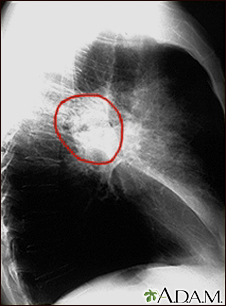

Lung cancer - small cell

SCLC is the most aggressive form of lung cancer. It usually starts in the breathing tubes (bronchi) in the center of the chest. Although the cancer cells are small, they grow very quickly and create large tumors. These tumors often spread rapidly (metastasize) to other parts of the body, including the brain, liver, and bone.